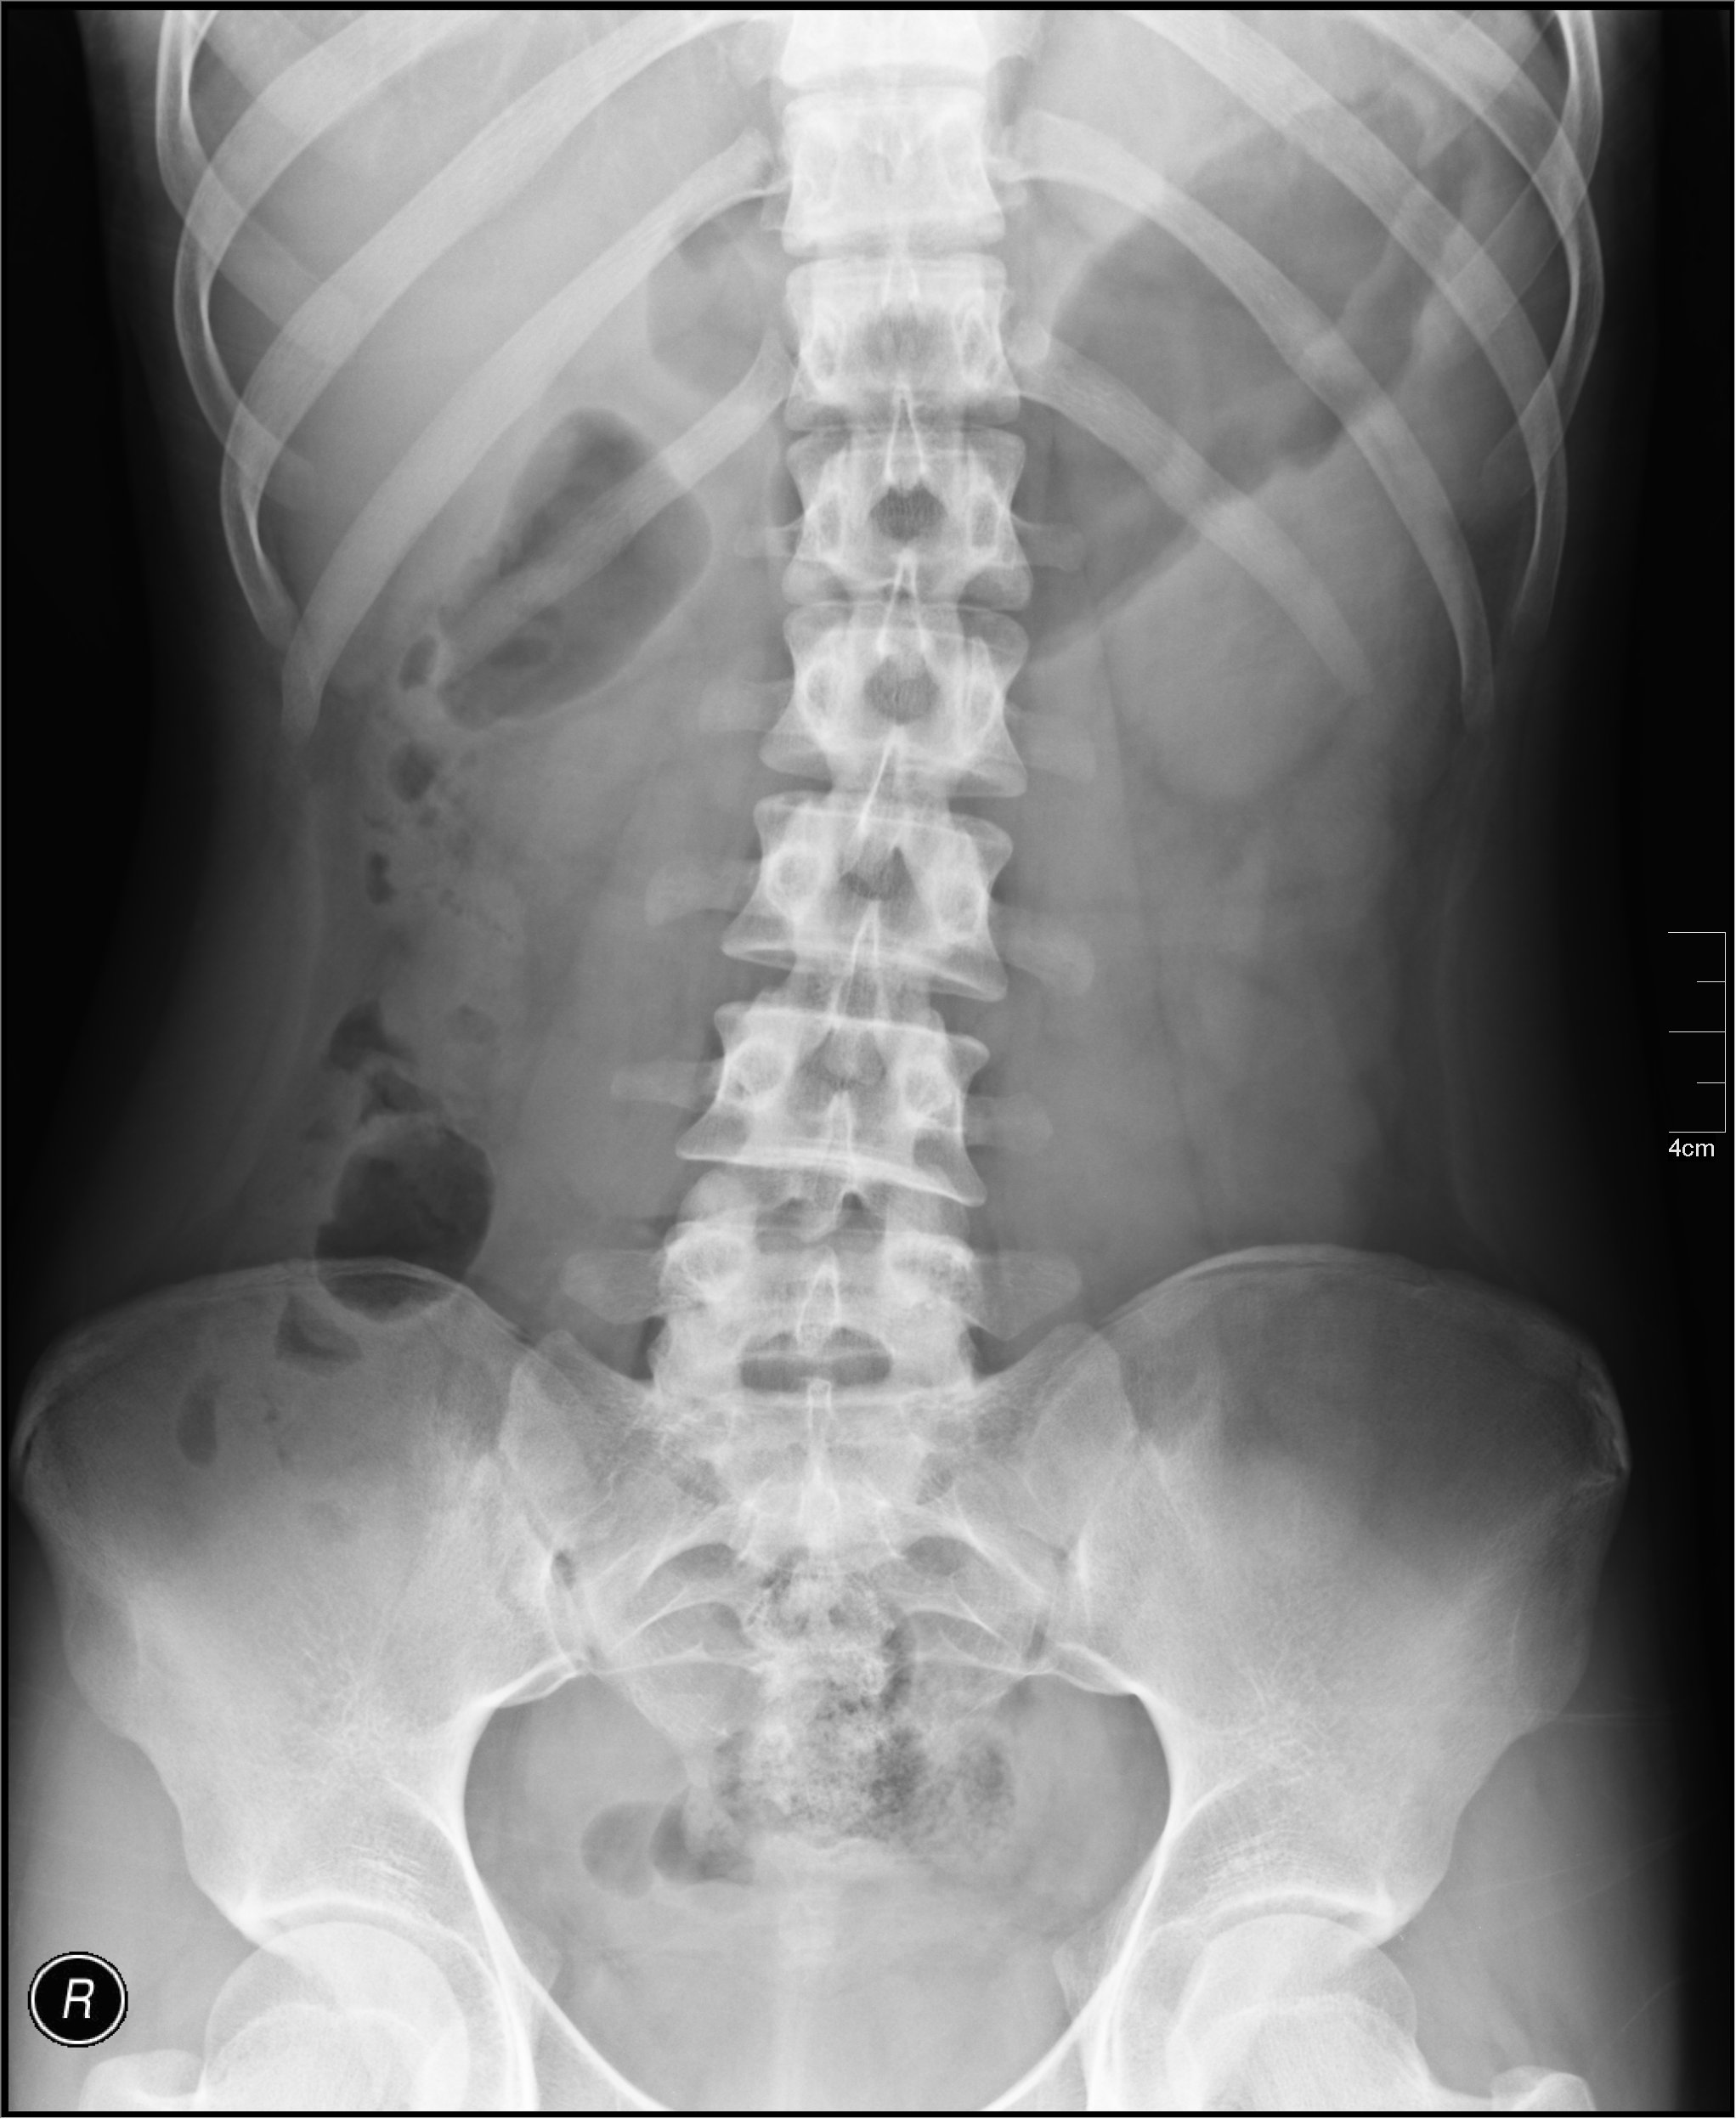

Acute abdominal series

- Differs from KUB in that patient is upright vs supine on KUB

- Supine abd film: width of bowel loops most visible (estimate of amount of distention)

Bowel Diameters: 3/6/9 rule

- Small bowel - 3 cm

- Colon - 6 cm

- Cecum - 9 cm